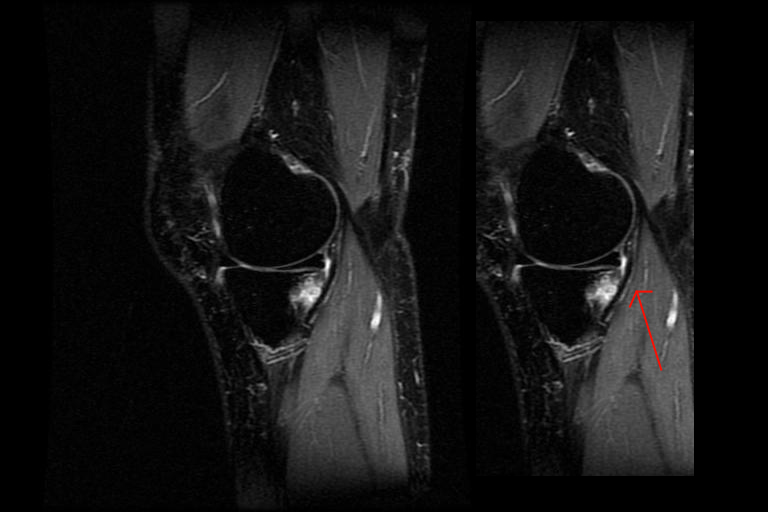

Magnetic resonance imaging mri is a technology often used to investigate the sources of knee problems.

Your doctor can use this test to diagnose you or to. It works by emitting magnetic waves that bounce off tissue bones and organs in different ways. While mri and arthroscopy have a close correlation x ray films tend to be less inductive of similar mri results.